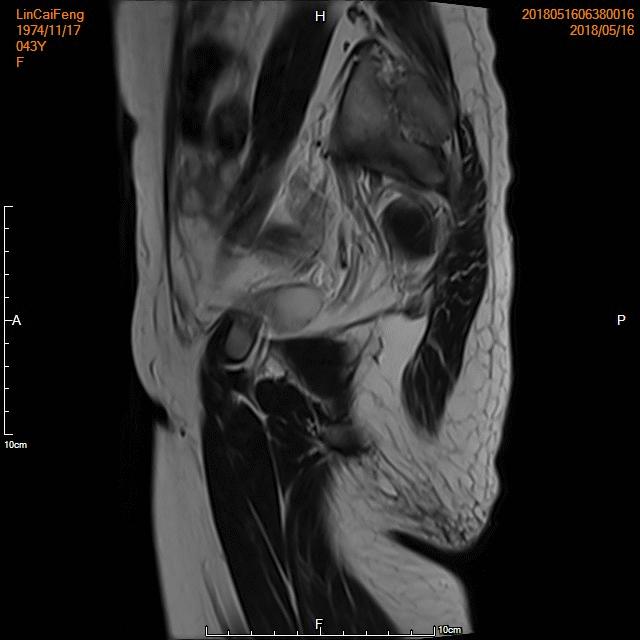

- 术前MRI检查显示子宫明显增大。

术前MRI检查显示子宫明显增大

- 术后4个月复查,子宫明显缩小,腺肌瘤明显坏死吸收,相关症状基本消失。

术后复查MRI显示子宫明显缩小,腺肌瘤明显坏死吸收